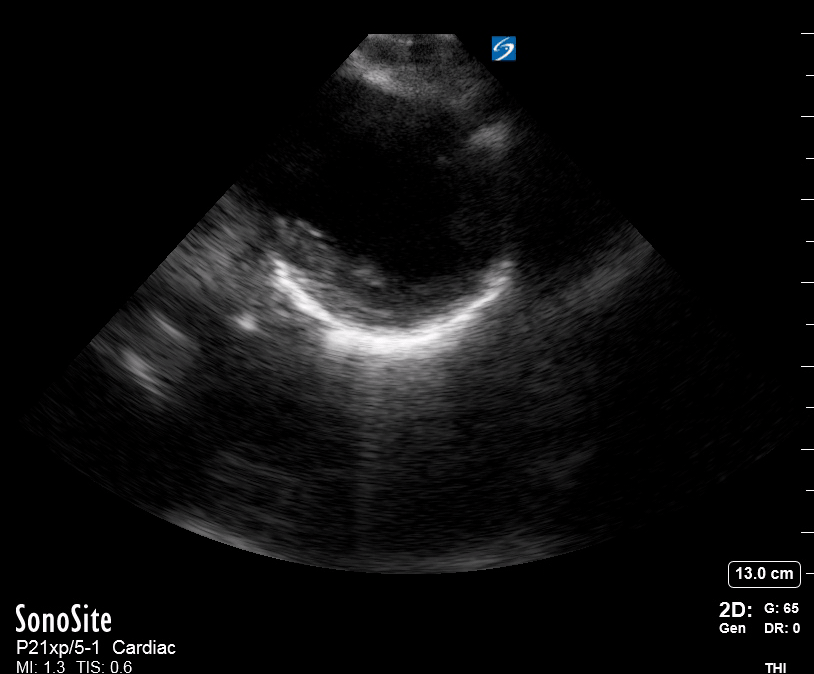

E-POINT SEPTAL SEPARATION

Active movement of the MV anterior leaflet during diastole, so it nearly touches the septum, correlates with good LV filling and ejection fraction. This can be assessed objectively by measuring the E-point septal separation (EPSS), which is the distance between the septum and the mitral anterior leaflet either in B-mode or M-mode. EPSS < 7mm is considered normal. EPSS is a good surrogate measure of ejection fraction, but it should be used with caution, as septal hypertrophy and mitral valve stenosis can lead to wrong estimations. In the PLAX view, it is important to have the septum lying horizontally flat on the image, as an oblique orientation may result in an overestimation of the EPSS.

Depiction of E-point septal separation: M-mode is used to measure the distance between the open mitral valve and the ventricular septum. Measurements greater than 7 mm are suggestive of depressed systolic ejection. (1. RV free wall, 2. Interventricular septum, 3. Mitral valve, 4. LV free wall). From: The "5Es" of emergency physician-performed focused cardiac ultrasound (11).